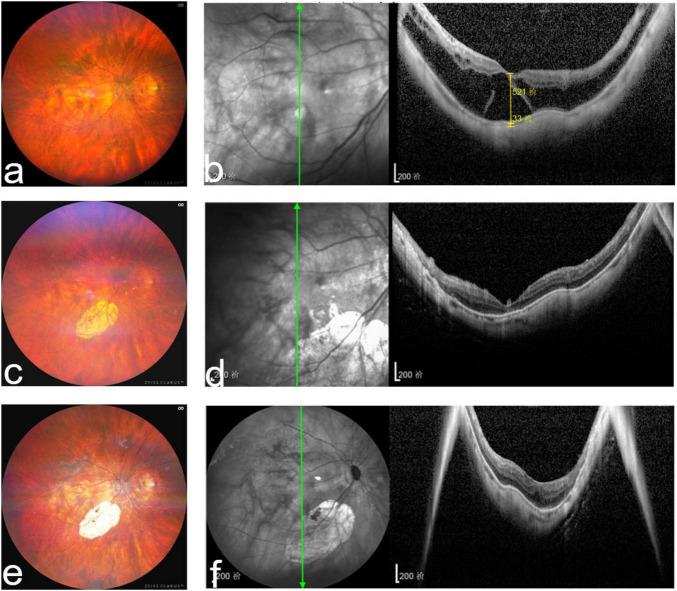

玻璃体切除术联合硅油或全氟丙烷(C3F8)填塞是治疗近视性中央凹裂合并中央凹脱离(MFFD)的标准方法。在本研究中,我们比较了采用硅油或C3F8填塞玻璃体切除术的MFFD患者术前和术后最佳矫正视力(BCVA)和最大中央凹厚度(MaxFT)。方法:所有患者均行眼科综合检查,包括BCVA测量、轴向测量、验光、眼压、裂隙灯检查、眼底检查、光学相干断层扫描。MFFD患者分为两组。所有患者均行23号玻璃体切割术,保留中央凹内限制膜剥离,并进行液气交换。一组用硅油填塞,另一组用C3F8填塞。在MFFD完全溶解后,硅油被完全去除。当玻璃体切除术或硅油去除术中发现晶状体混浊时,进行超声乳化术合并人工晶状体植入术。分别于术后1、3、6、12个月评估BCVA和MaxFT。使用硅油的患者在去除硅油3个月后进行额外评估。所有数据均使用GraphPad Prism计算。结果:41例患者共41只眼纳入研究。硅油组18只眼,C3F8组23只眼。两组术后1、3、6、12个月BCVA和MaxFT均有显著改善。两组术后BCVA、MaxFT无显著差异。硅油组和C3F8组分别有6例和3例短暂性高眼压。C3F8组1例出现黄斑孔。两组患者均无其他并发症。结论:玻璃体切除术联合保留中央窝内限制膜剥离、硅油或C3F8填塞是治疗MFFD有效、实用的方法。

Methods: All patients underwent comprehensive ophthalmological examinations, including measurement of BCVA, axial measurement, optometry, intraocular pressure, slit-lamp examination, fundus examination, and optical coherence tomography. Patients with MFFD were divided into two groups. All patients underwent with 23-gauge pars plana vitrectomy with fovea-sparing internal limiting membrane peeling, and fluid-air exchange. One group underwent tamponade with silicone oil, whereas the other group underwent tamponade with C3F8. The silicone oil was completely removed upon complete resolution of MFFD. Phacoemulsification with intraocular lens implantation was performed when a lens opacity was noted during vitrectomy or along with silicone oil removal. BCVA and MaxFT were assessed at 1, 3, 6, and 12-months post-operatively. Patients with silicone oil were additionally assessed 3-months after silicone oil removal. All data were calculated using GraphPad Prism.

Results: Forty-one patients with 41 eyes were enrolled in the study. Eighteen eyes were included in the silicone oil group, whereas 23 eyes were included in the C3F8 group. Both groups demonstrated significant improvement in BCVA and MaxFT at 1, 3, 6, and 12-months post-operatively. There was no significant difference in BCVA and MaxFT between both groups post-operatively. Transient ocular hypertension was noted in six and three cases in the silicone oil and C3F8 groups, respectively. One case in the C3F8 group developed a macular hole. There were no other complications in the two groups.